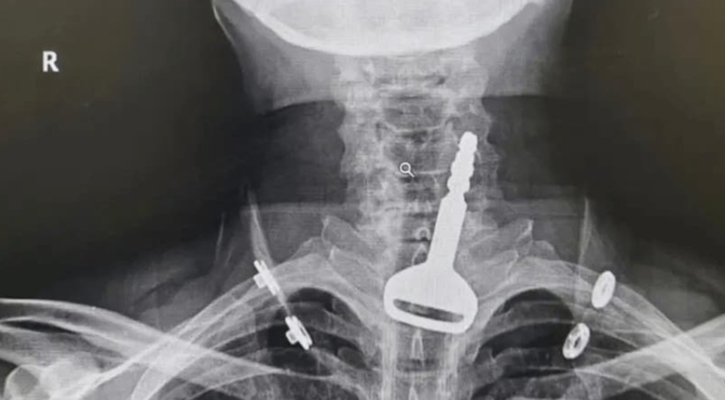

খেলার ছলে মুখের ভেতর গাড়ির চাবি নিয়ে জিহ্বা দিয়ে নাড়াচাড়া করছিলেন। এমন সময় ওই চাবি গলার ভেতর ঢুকে আটকে গেল শ্বাসনালিতে।